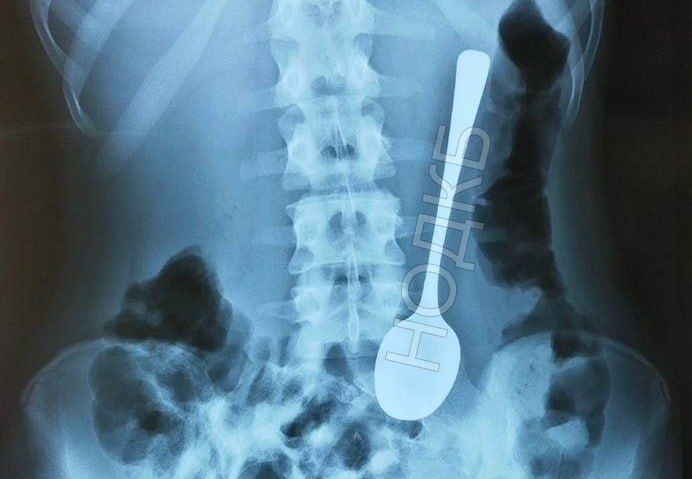

Ребенок проглотил чайную ложку в Нижнем Новгороде

Нижегородский врач-эндоскопист, заведующий отделением НОДКБ Александр Дворянинов извлек из желудка ребенка проглоченную им чайную ложку. Об этом сообщает в Telegram представитель сферы здравоохранения Алексей Никонов.

Когда эндоскописту позвонили хирурги и рассказали про ребенка с десертной ложкой в желудке, который ожидает в приемном покое, Александр Дворянинов сначала принял это за шутку. Однако это оказалось правдой.

Врач аккуратно извлек инородное тело с помощью гастроскопа. Ребенку даже не потребовалось давать наркоз. Медсестры, которые давно работали в больнице, отметили, что таких случаев больше не было. Сейчас ложка заняла место в музее инородных тел НОДКБ.